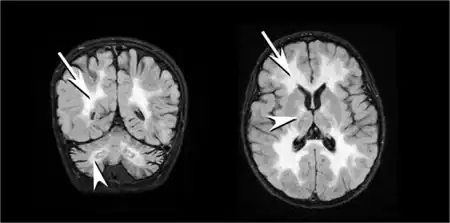

| T2 weighted axial scan of a human brain at the level of the caudate heads demonstrates marked loss of posterior white matter, with reduced volume and increased signal intensity. The anterior white matter is spared. Features are consistent with X-linked adrenoleukodystrophy. | |

The degeneration of white matter, which reflects the degeneration of myelin, can be seen in a basic MRI and used to diagnose leukodystrophies of all types. T-1 and T-2 weighted fluid-attenuated inversion recovery (FLAIR) images are the most often used approach.[26] Electrophysiological and other kinds of laboratory testing can also be done. In particular, nerve conduction velocity is looked at to distinguish between leukodystrophy and other demyelinating diseases, as well as to distinguish between individual leukodystrophies. For example, individuals with X-ALD have normal conduction velocities, while those with Krabbe disease or metachromatic leukodystrophy have abnormalities in their conduction velocities.[26] Multigene sequencing panels for undifferentiated leukodystrophy are offered for rapid molecular diagnosis after genetic counselling.